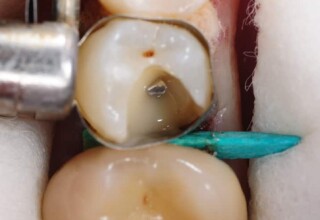

Posterior Tooth Root Canal Restoration with a Composite Resin Filling

The common restoration of a posterior tooth after a root canal is a crown. Its main purpose is to protect from fracture and concomitant extraction. In very few cases that specific criteria (mainly remaining tooth structure) are met or where finances predominate, an extensive composite filling can restore both aesthetics and function.

Restoration of a cracked molar with composite resin

Cracked teeth present a challenge in restorative dentistry both from the aspect of complexity of the restoration itself (usually large filings) and the necessary providings to avoid a complete fracture. The presented case demonstrates the simplest approach of a bonded direct restoration with composite resin. It is based on the principle of an adhesive filling that “holds” the remaining tooth structures “together”. The restored molar remained healthy for two years, then required a root canal and a crown was placed for maximum protection.